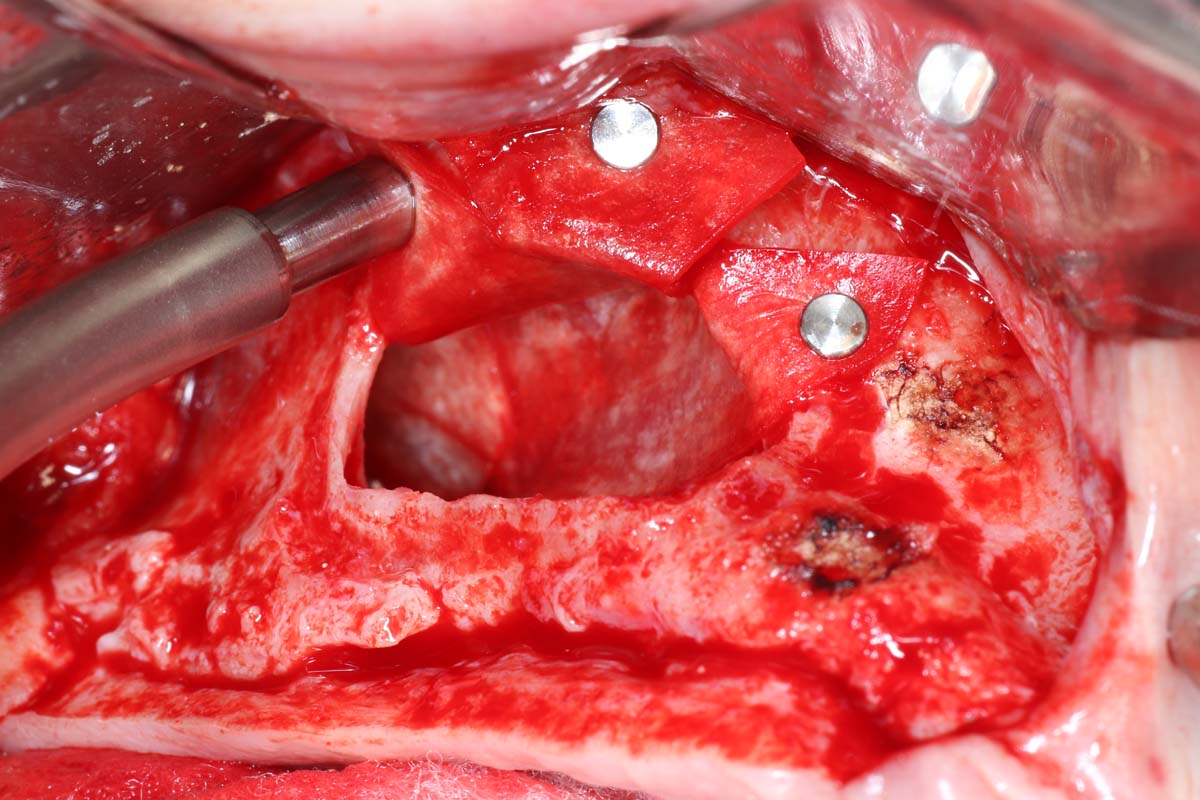

Gain Hands-On Skills and Watch Live Surgery to Master Implant Site Development Techniques

Elevate your skills in implant site development with hands-on practice and live surgical demonstrations. Observe procedures in real time and participate in practical sessions to build confidence in essential techniques, from bone grafting to soft tissue management.

- Indications and step by step surgical protocol for sinus bone grafting – lateral and crestal approach.

- Comprehensive recognition, management, and treatment of intraoperative, early and late postoperative complications.